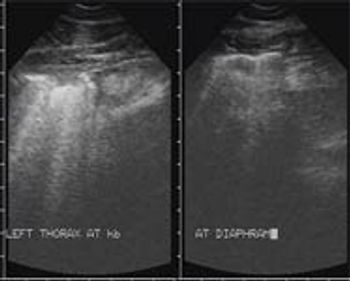

This case represents what clinical impression indicates is the most common form of pleuropneumonia seen in equine practice.